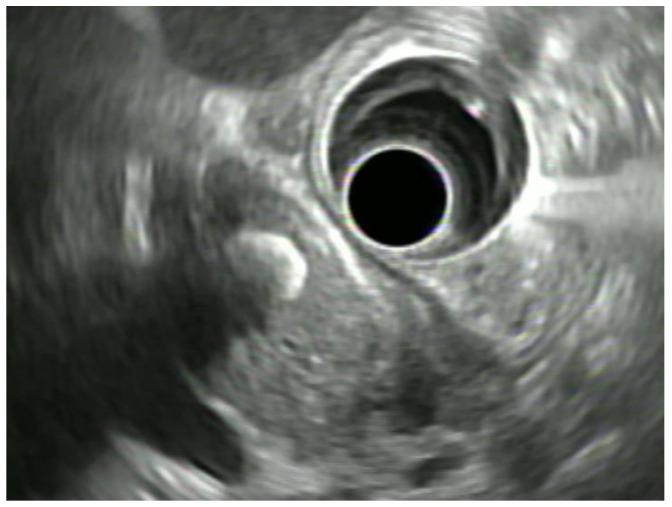

Biliary diseases are common, but clinical symptoms are often unspecific and direct access and visualization of the biliopancreatic system for diagnostic purpose is difficult. In the last decades endoscopic ultrasound (EUS) has become a primary method in the gastrointestinal tract. It significantly changed the role of endoscopy in diagnostic imaging in the gastrointestinal tract and adjacent organs. EUS has become an effective diagnostic tool in biliary stone disease as well as in the diagnosis of indeterminate biliary strictures. Furthermore, an EUS-directed transmural approach emerged as a safe and effective alternative to ERCP in patients requiring biliary drainage, in particular as a backup method if standard ERCP-approach fails. Development of new techniques, specific accessories and stents during the last decade led to an enormous step forward in terms of efficacy and safety of an EUS-directed approach. In the current article technical and clinical aspects of EUS-guided diagnostic and therapeutic approaches in different clinical indications will be discussed together with a review of the available data.

胆道疾病很常见,但临床症状往往不具特异性,且为诊断目的直接进入和可视化胆胰系统很困难。在过去几十年中,内镜超声(EUS)已成为胃肠道的主要检查方法。它显著改变了内镜在胃肠道及邻近器官诊断成像中的作用。EUS已成为胆石症以及不明原因胆管狭窄诊断的有效工具。此外,在需要胆道引流的患者中,EUS引导的经壁入路已成为一种安全有效的替代内镜逆行胰胆管造影(ERCP)的方法,特别是在标准ERCP方法失败时作为备用方法。过去十年中新技术、特定附件和支架的发展,在EUS引导方法的有效性和安全性方面取得了巨大进展。在本文中,将讨论EUS引导的诊断和治疗方法在不同临床适应症中的技术和临床方面,并对现有数据进行综述。